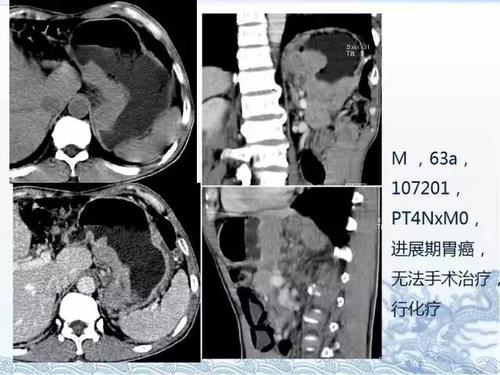

ct检查及诊断攻略——胃癌,结直肠癌

ct检查及诊断攻略胃癌结直肠癌